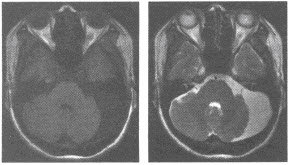

患者,男,73岁。入院诊断:急性阑尾炎并行急诊阑尾切除。术后腹痛症状不改善,不排气、不排便3天。行钡灌肠检查,如图。

(单选题)该患者最可能的诊断是()

E:乙状结肠扭转